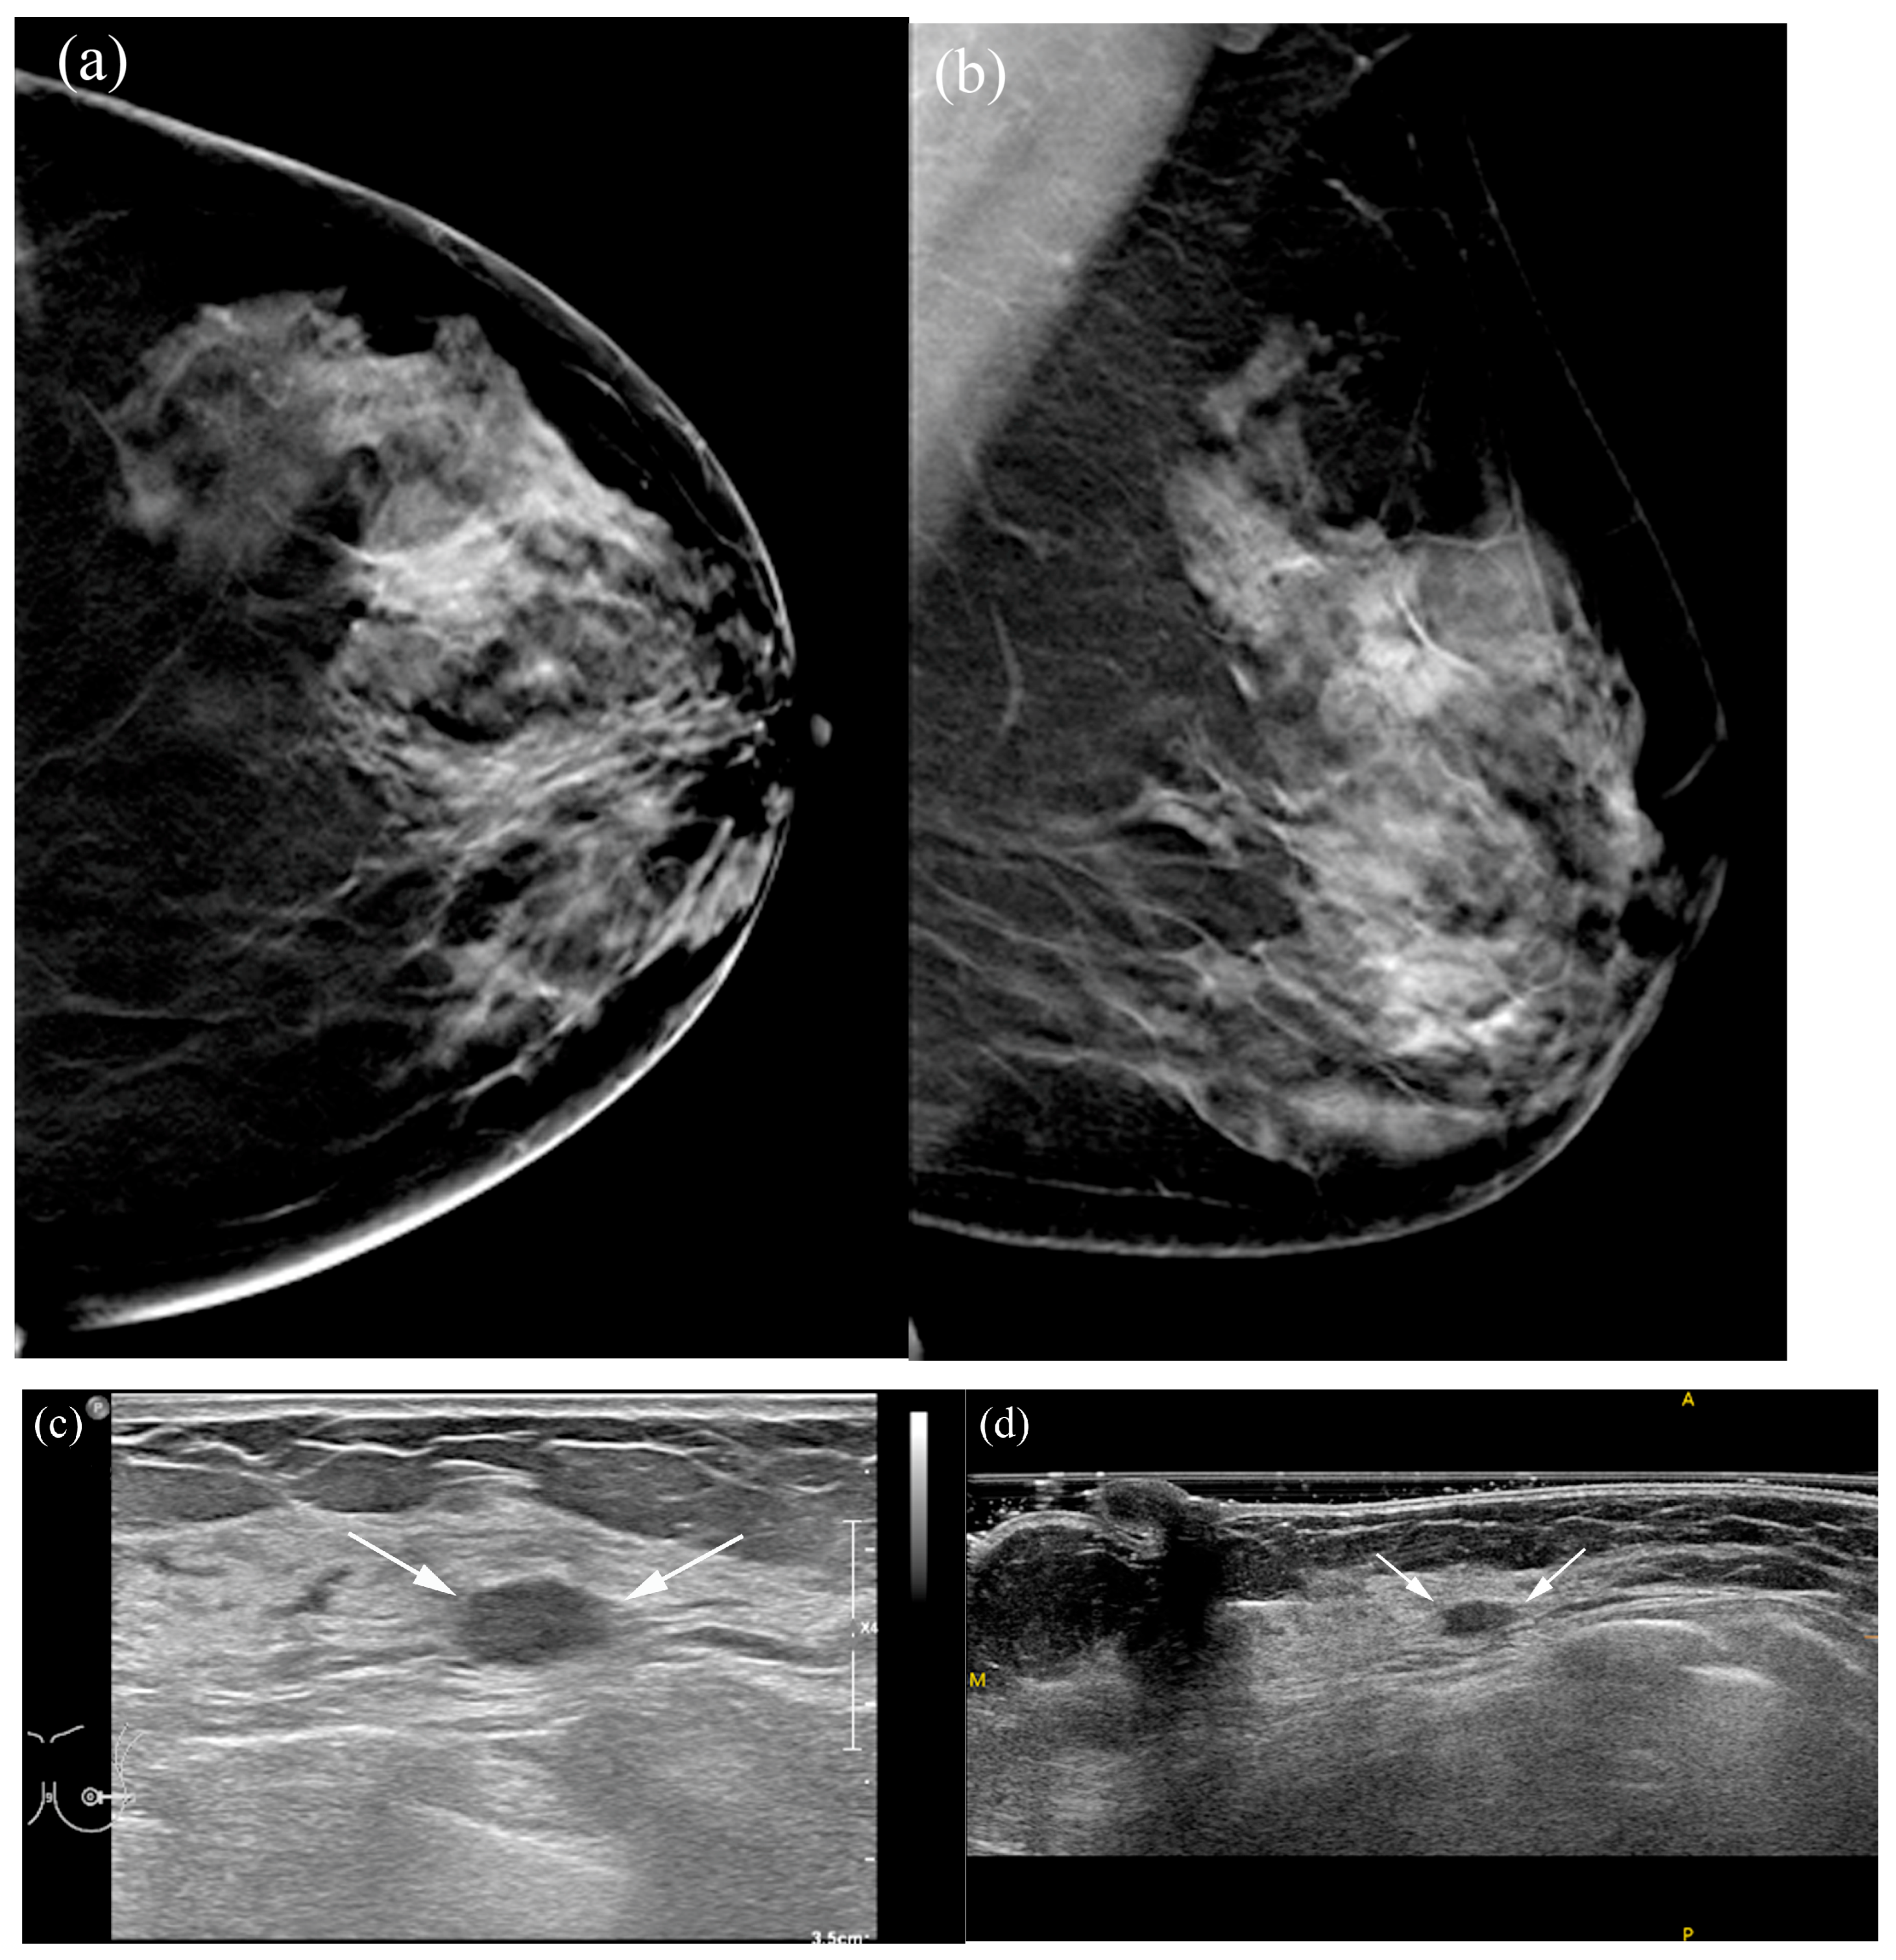

Figure 4. A 66-year-old female patient with screen-detected invasive lobular and ductal carcinoma: (a,b) The malignancy is not visualized on digital breast tomosynthesis (DBT). (c) Hand-held ultrasound reveals a spiculated, irregular, heterogeneous hypoechoic mass (arrows) in the left 12 o’clock area. (d,e) MammouS-N transverse images in craniocaudal (d) and mediolateral oblique (e) views demonstrate an indistinct, irregular, heterogeneous hypoechoic mass (arrows) in the central upper area of the left breast. S = superior, I = inferior, and M = medial.

Table 5 summarizes the factors influencing lesion visibility on DBT and MammouS-N images. Lesions that were better visualized on MammouS-N included masses obscured on DBT and non-calcified lesions (p ≤ 0.005) (Figure 4 and Figure 5). Reviewer 2’s assessment showed that larger lesions tended to be better visualized using DBT. No significant associations were observed between lesion visibility and factors such as patient age, mammographic density, lesion size on MammouS-N, echotexture, or lesion type (Figure 6).

Lesion characteristics strongly influenced the visibility differences between the two modalities. Non-calcified lesions received high visibility scores on both DBT and MammouS-N, according to both reviewers. However, DBT demonstrated superior performance in detecting calcified lesions, accounting for 44% of the cases in this study. This result was expected, as tomosynthesis is particularly effective for detecting calcifications owing to its high-contrast appearance, whereas ultrasound generally has limited sensitivity for microcalcifications unless they are associated with a mass or non-mass lesion [14,15]. On MammouS-N, 93% of the lesions were classified as masses, and only 7% were classified as non-mass lesions. This distribution suggests that MammouS-N may be particularly valuable for enhancing the detection and characterization of mass lesions, particularly smaller lesions without associated calcifications, which may be more challenging to identify using DBT.